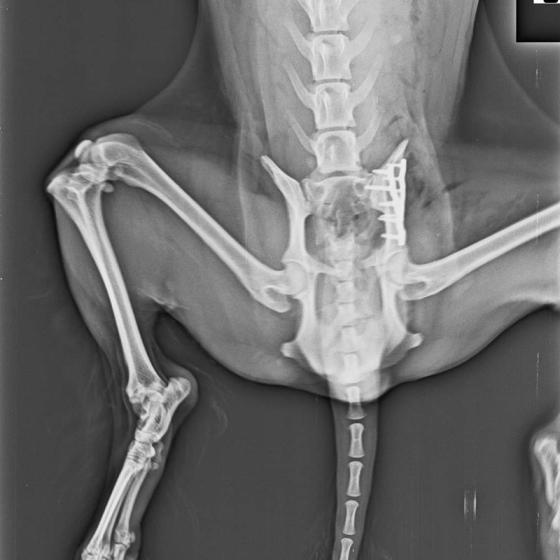

Bola neskutočne zanedbaná, hladná a dolámaná. Panvu má zlomenú na troch miestach, od úderu jej praskol močový mechúr a mala na sebe snáď všetky blchy sveta, žrali ju zaživa. Zotavuje sa.. Pomaličky, ale zotavuje sa po náročných operáciách a dúfame, že bude opäť v poriadku. Bude potrebovať rehabilitovať, aby vedela opäť behať, ale zabezpečíme jej úplne všetko, čo bude treba!!

A teraz si kladiete otázku, že prečo my a nie pôvodná rodina, že? Lebo sme tu pre to aby sme pomohli psíkom, ktorí majiteľa nemajú, alebo ich majitelia nemajú možnosť pomôcť im. Rodina sa s Miou musela rozlúčiť pred rokom z vážnych dôvodov, ktoré samozrejme rozoberať nebudeme. Mia má teraz nás a samozrejme Vás. Je to skromné, pokorné a neskutočne prítulné stvorenie, ktoré so sebou i napriek bolestiam nechá robiť čokoľvek lebo vie, že sa to robí v jej záujme. Mimi (ako ju volám) bude mať 17.5.2021 šieste narodeniny a dala som jej sľub, že poprosím dobrých ľudí, aby sme oslavovali spolu jej nový začiatok. Prijali sme ju pod naše združenie s vierou, že keď sa spojíme pre jej dobro, zvládneme náklady na operácie a rehabilitácie. Pomôžete nám prosím? Sú to opäť nečakané náklady, na ktoré sme neboli pripravené, úspory žiaľ už nemáme žiadne a príjem z 2% je ešte v nedohľadne. Prikladáme aj Miuškinu faktúru za ortopedickú operáciu, rekonštrukciu panvy. Faktúru za operáciu prasknutého mechúra ešte nemáme, a s rehabilitáciou ešte iba začneme. Pomôže nám ozaj každé euro.